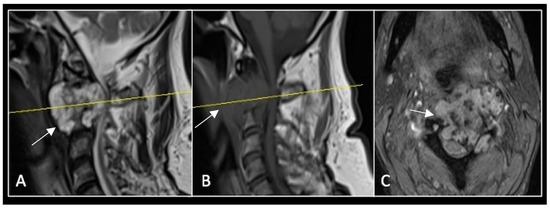

Figure 11.

RI demonstrating a lobulated destructive lesion (arrow) with significant epidural extension and compression at L2. The yellow line on the sagittal images denotes the level of the axial image. (A) T2W sagittal; (B) T1W sagittal; (C) T2W axial.

Figure 13.

A 6-month postoperative surveillance MRI shows no obvious evidence of residual tumour (arrow) disease progression, but there is significant artefact. The yellow line on the sagittal images denotes the level of the axial image. (A) T2W sagittal; (B) T1W sagittal; (C) T2W axial.

Figure 14.

A 12-month postoperative surveillance MRI shows no evidence of residual tumour (arrow) disease progression. The severity of artefact is reduced. The yellow line on the sagittal images denotes the level of the axial image. (A) T2W sagittal; (B) T1W sagittal; (C) T2W axial.